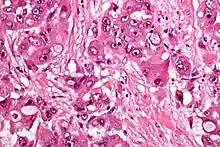

| Micrograph of fibrolamellar hepatocarcinoma showing the characteristic laminated fibrosis between the tumor cells with a low NC ratio. H&E stain. | |

The histopathology of FLC is characterized by laminated fibrous layers, interspersed between the tumor cells. Cytologically, the tumor cells have a low nuclear to cytoplasmic ratio with abundant eosinophilic cytoplasm.[1] Tumors are non-encapsulated, but well circumscribed, when compared to conventional HCC (which typically has an invasive border).

Intermed. mag.

Intermed. mag. High mag.